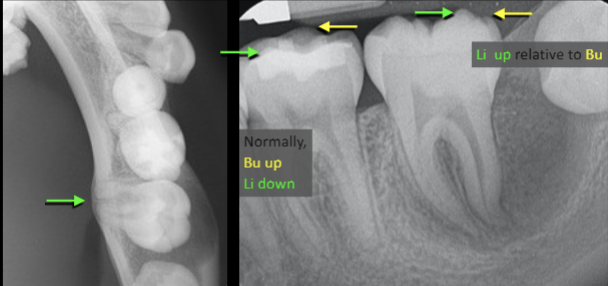

What cyst has a tooth that remains vital, root displaced lingually, and lingual cusps appear higher than buccal cusps and PAs and BWs?

Buccal Bifurcation Cyst

Describe the radiographic features of this Buccal Bifurcation Cyst?

Buccal Bifurcation of Molars

Roots Displaced Lingually

Occlusal Plane Inclined Buccally

Lingual Cusp Higher on BWs and PAs